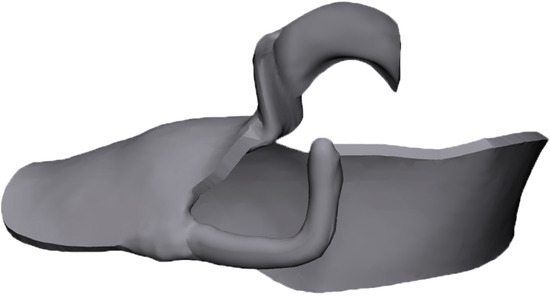

2.1. FE Models